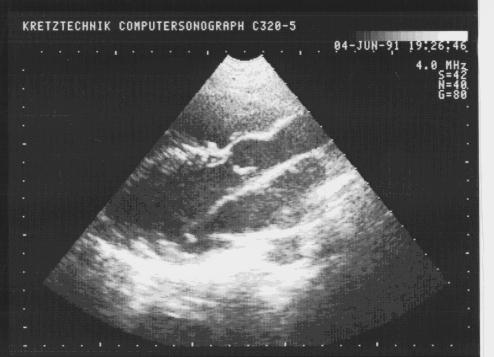

Открытый артериальный проток.

Рис.92.

Открытый

артериальный

проток.

Прямая визуализация протока из надгрудинного доступа в виде эхосвободного пространства между нисходящей аортой и легочной артерией.